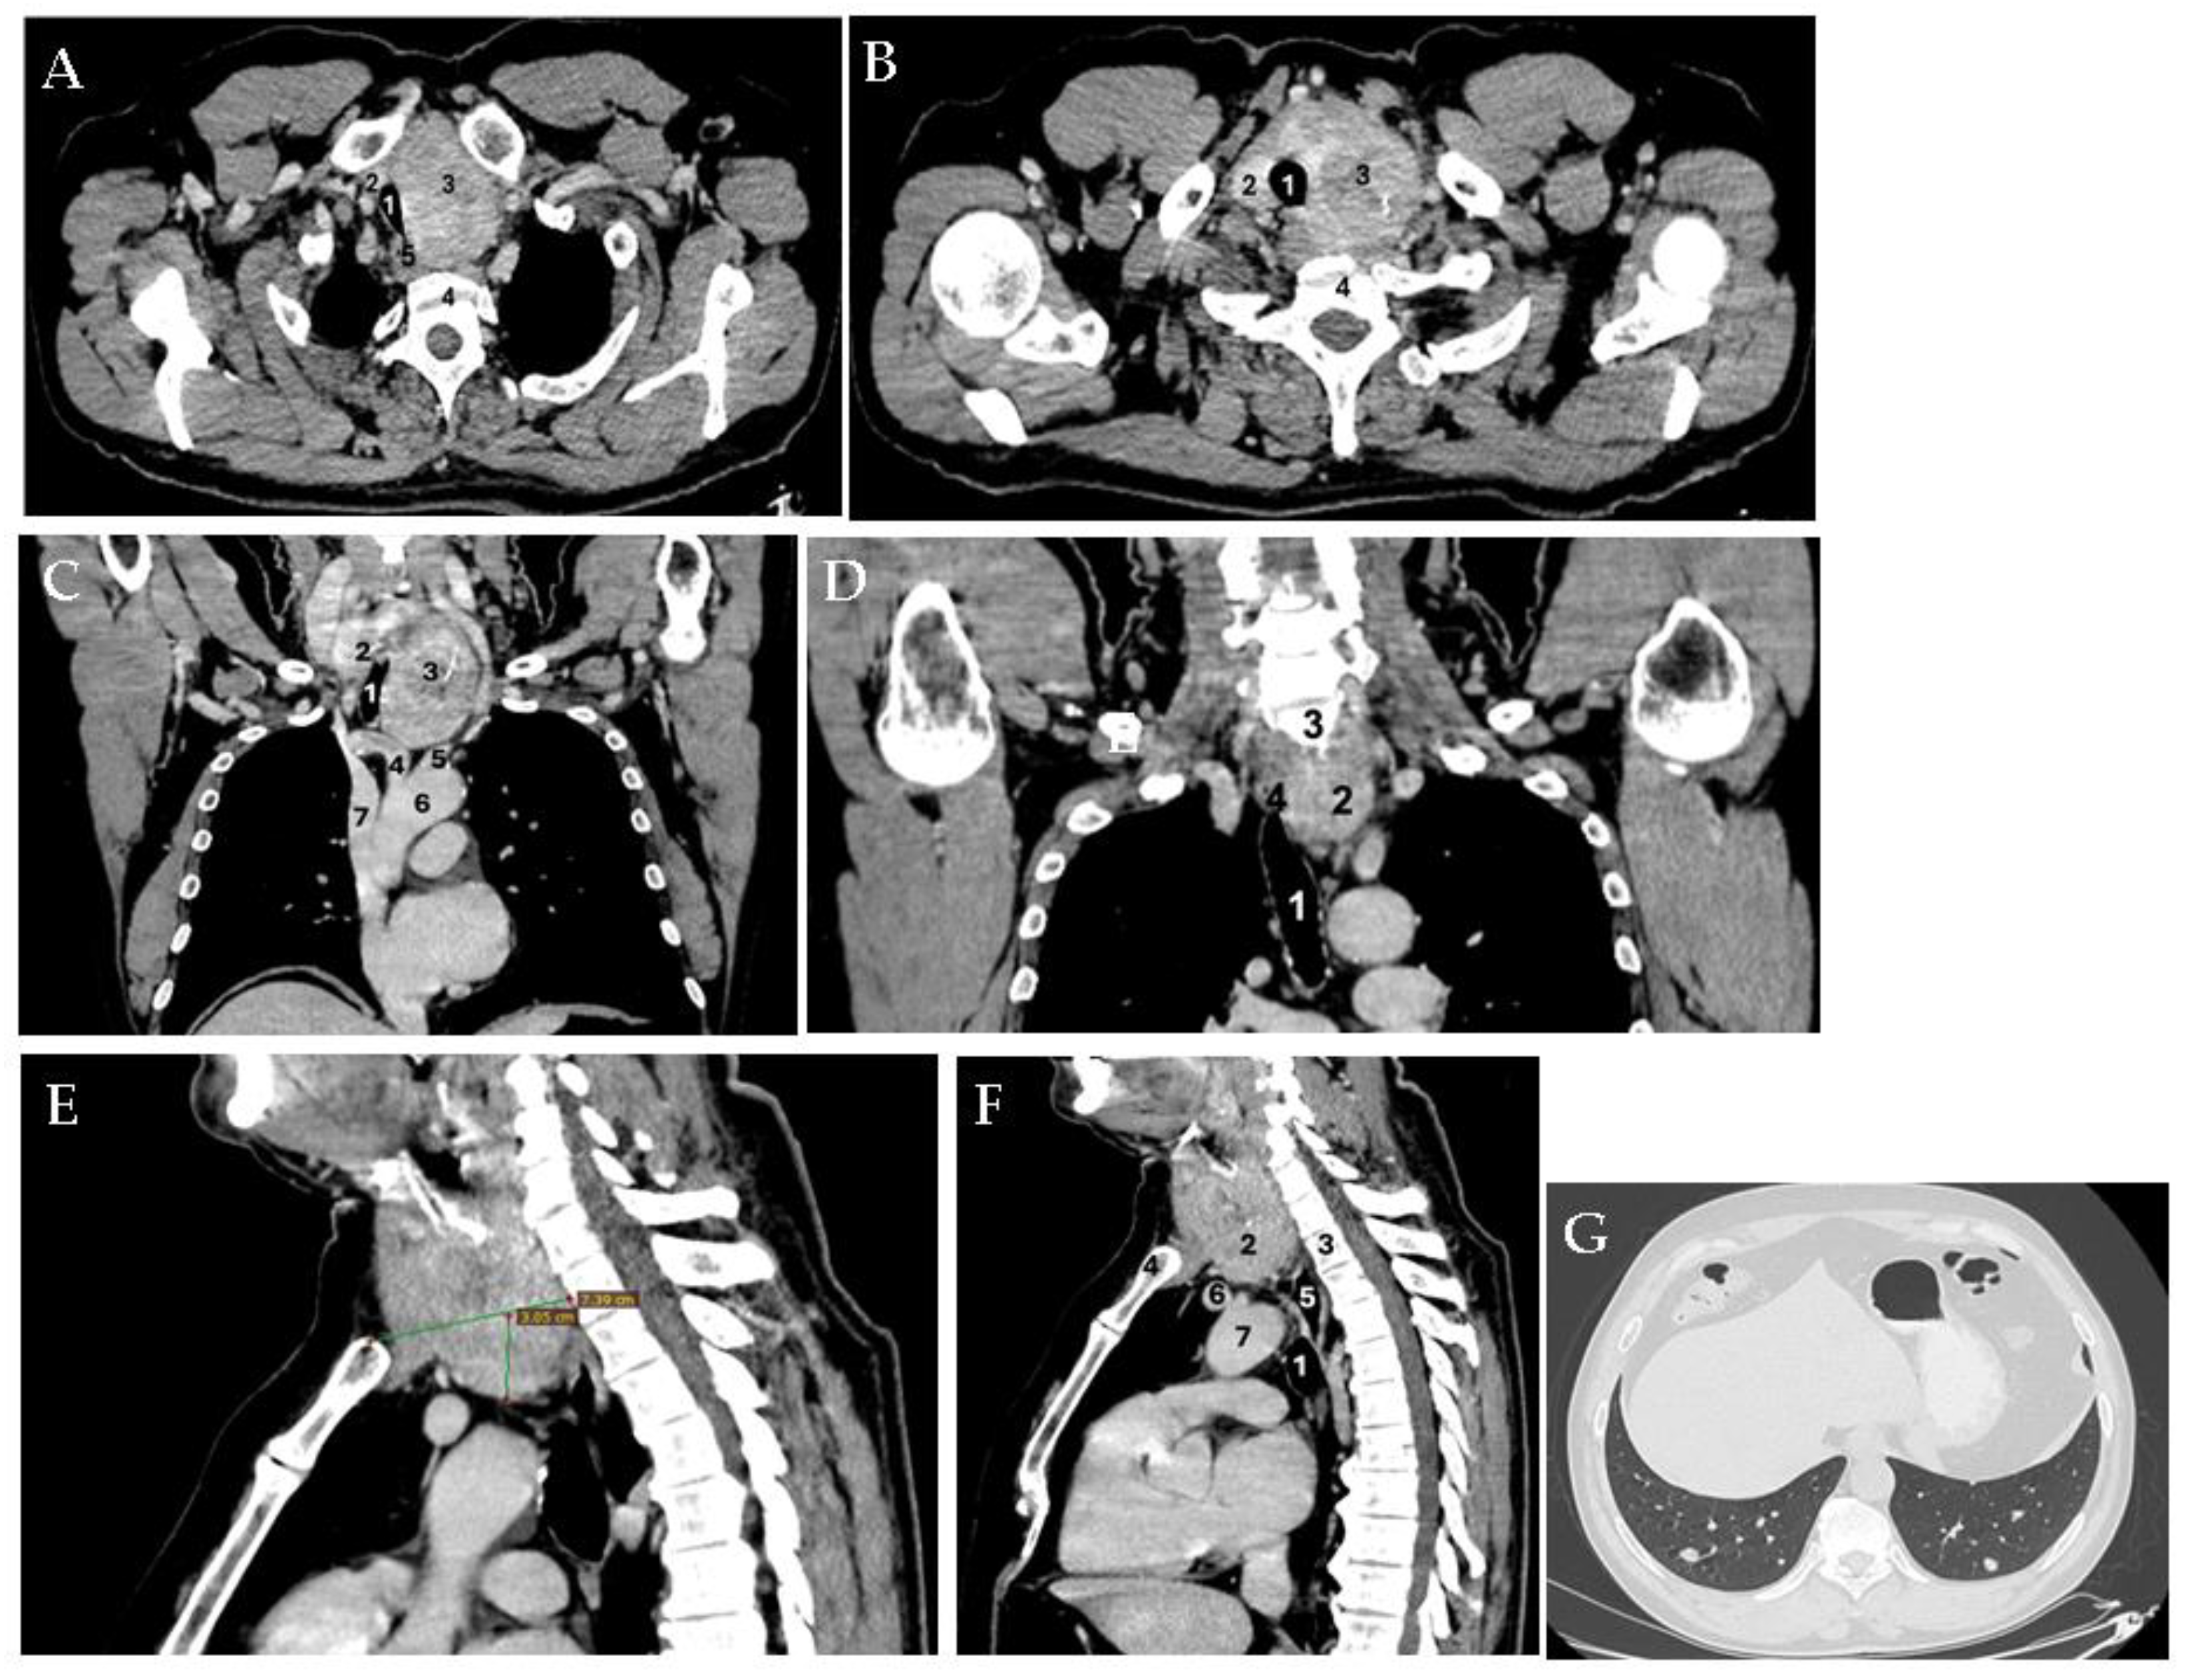

Multilayered Insights into Poorly Differentiated, BRAFV600E-Positive, Thyroid Carcinoma in a Rapidly Developing Goiter with Retrosternal Extension: From En “Y” Cervicotomy to SPECT/CT-Positive Lung Metastases

Sima, O.-C.; Cucu, A.-P.; Terzea, D.; Nistor, C.; Vasilescu, F.; Eftimie, L.-G.; Ciobica, M.-L.; Costachescu, M.; Carsote, M. Multilayered Insights into Poorly Differentiated, BRAFV600E-Positive, Thyroid Carcinoma in a Rapidly Developing Goiter with Retrosternal Extension: From En “Y” Cervicotomy to SPECT/CT-Positive Lung Metastases. Diagnostics 2025, 15, 2049. https://doi.org/10.3390/diagnostics15162049